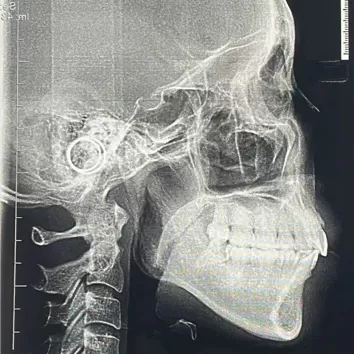

Rayons X avant le traitement

[Radiographie panoramique/Céphalogramme latéral]